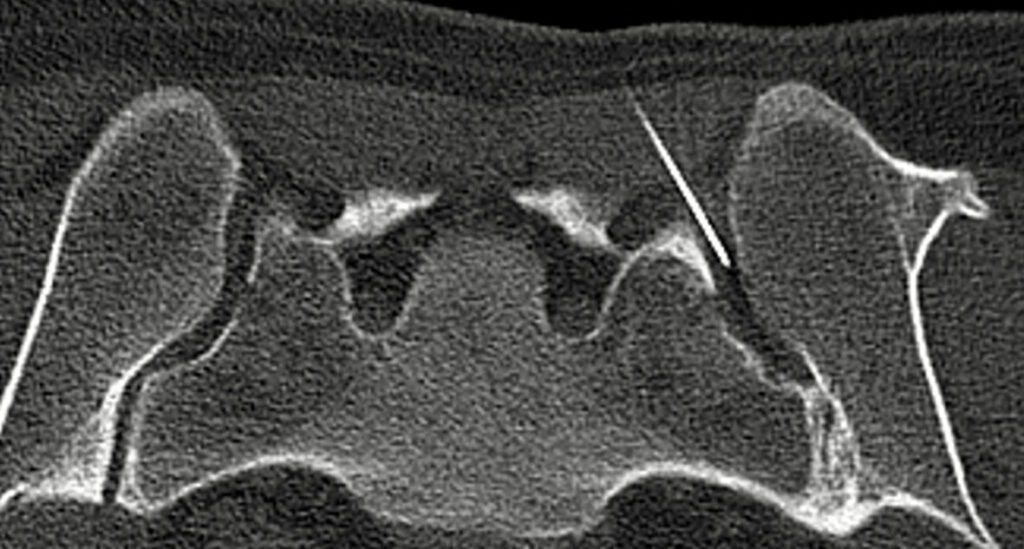

CT (Computertomographie)

→ Arthrographie der Schulter, Hüfte und Sprunggelenk

→ CT-gesteuerte minimalinvasive Schmerztherapie der LWS, ISG, Becken und Hüfte